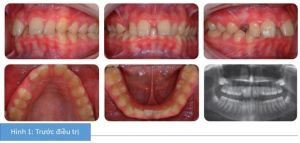

Phân tích case: Niềng răng thành công cho bệnh nhân bị hô nhẹ có phanh môi bám thấp và khe thưa đường giữa

Bệnh nhân nữ 13 tuổi có tương quan răng cửa hạng II tiểu loại 1 với kiểu xương hạng II nhẹ, phức tạp bởi độ cắn chìa lớn và khe thưa đường giữa hàm trên, phanh môi bám thấp.